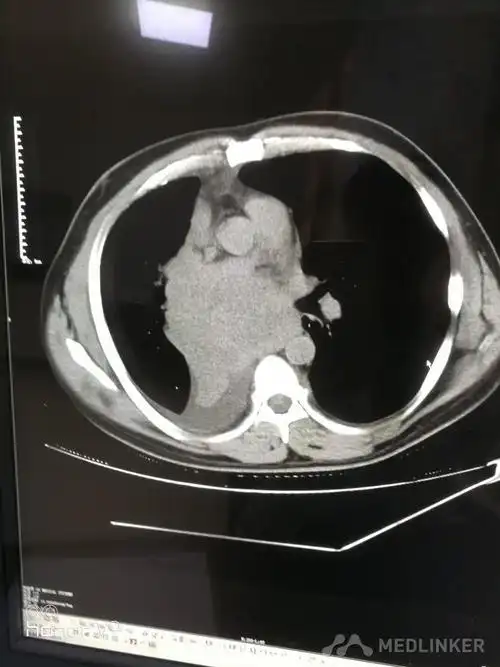

中央型肺癌肺内多发转移一例!

8cm,考虑中央型肺癌可能;纵隔多发增大淋巴结.

中央型肺癌的ct表现

ct诊断中央型肺癌伴心脏转移一例